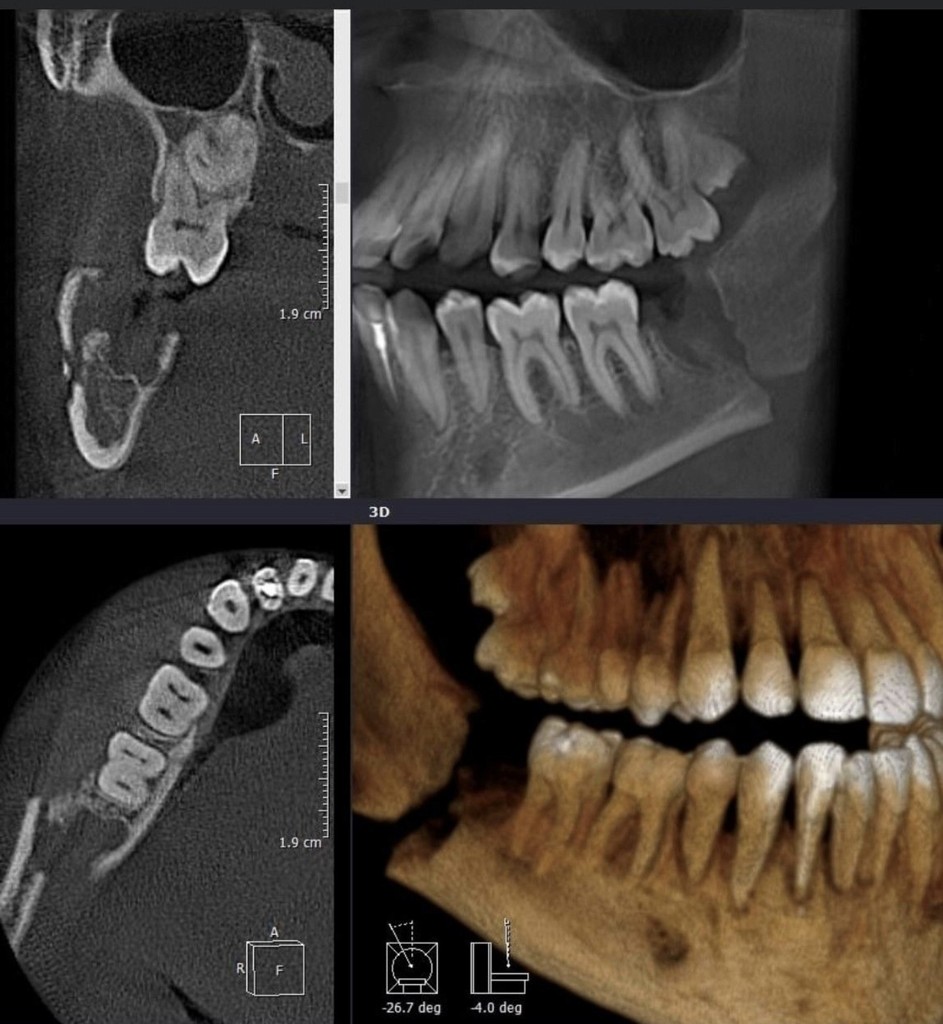

Роль КПКТ у діагностиці травм

Лінії розлому, зміщення, фрагментацію; етапи зрощення та нормальної консолідації

Ознаки переломів і оцінка консолідації